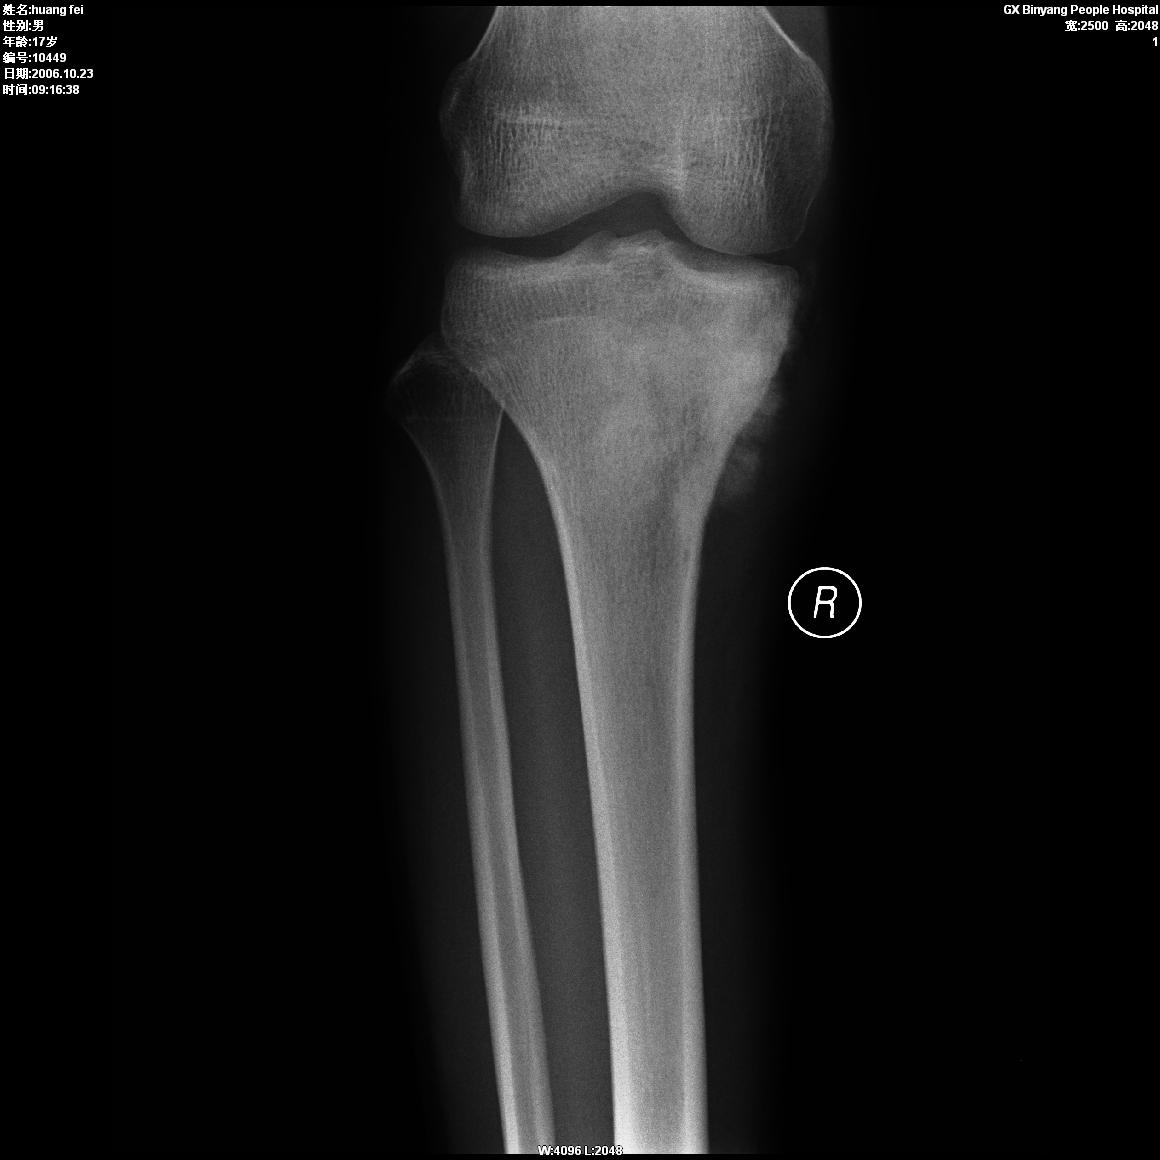

男,17岁。

单就影像看 胫骨近侧干骺端放射状骨膜反应,有成骨肉瘤的可能。还请楼主补充资料

片子体位不全,缺少病史,单依正位片看,警惕皮质旁骨肉瘤的可能,建议ct或加照侧位及切线位

感谢各位指点,病人17岁,右膝关节肿痛2个月.某三乙医院考虑硬化型骨髓炎.我只是寻求老大们的意见.谢谢!

片子体位不全,缺少病史,单依正位片看,胫骨近侧干骺端放射状骨膜反应,警惕皮质旁骨肉瘤的可能,建议ct或加照侧位及切线位

请楼主上传侧位或切线位片,另外上传软组织窗。局限性密度不均匀增高,骨膜增生不规则,似有肿瘤骨(图片软组织显示欠清),考虑硬化型骨肉瘤或皮质旁肉瘤。

年龄,好发部位及影像表现都符合成骨肉瘤x线诊断。缺点就是临床资料不完整,没有侧位。期待病理结果

胫骨近侧干骺端放射状骨膜反应,有成骨肉瘤的可能。还请楼主补充资料

单就影像看 胫骨近侧干骺端放射状骨膜反应,有成骨肉瘤的可能。

应考虑骨肉瘤(放射状骨膜增生、局限性密度不均匀、有软组织肿块、病史)